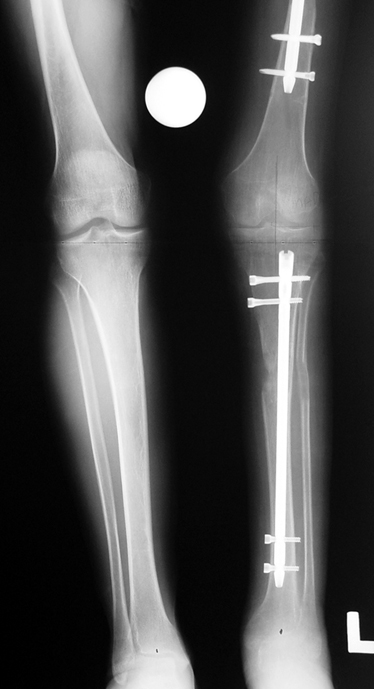

3- POSTTRAVMATİK BACAK KISALIĞI (YANLIŞ KAYNAMA)

Bu Bacak Kısalık tipi bir kırığın kısalmış pozisyonda kaynaması ile oluşur. Bir çok vaka yetişkinlerde görülür ve sadece bir uzatma ile tedavi edilebilir. Ek deformiteler de aynı anda düzeltilebilir. Bu hastaların çoğu çivi üzerinden uzatma veya tam implante edilen çivi ile tedavi edilebilirler.